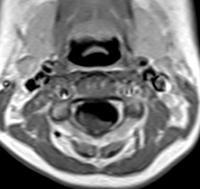

肠气囊肿(pneumatosis cystoids intestinalis,PCI)又称为囊样肠积气,是胃肠道的黏膜下或浆膜下出现气性囊肿,它可累及从食管至直肠的全部或部分胃肠道,但临床主要发病在小肠和结肠,亦可发生于肠系膜、大网膜,肝胃韧带和其他部位。